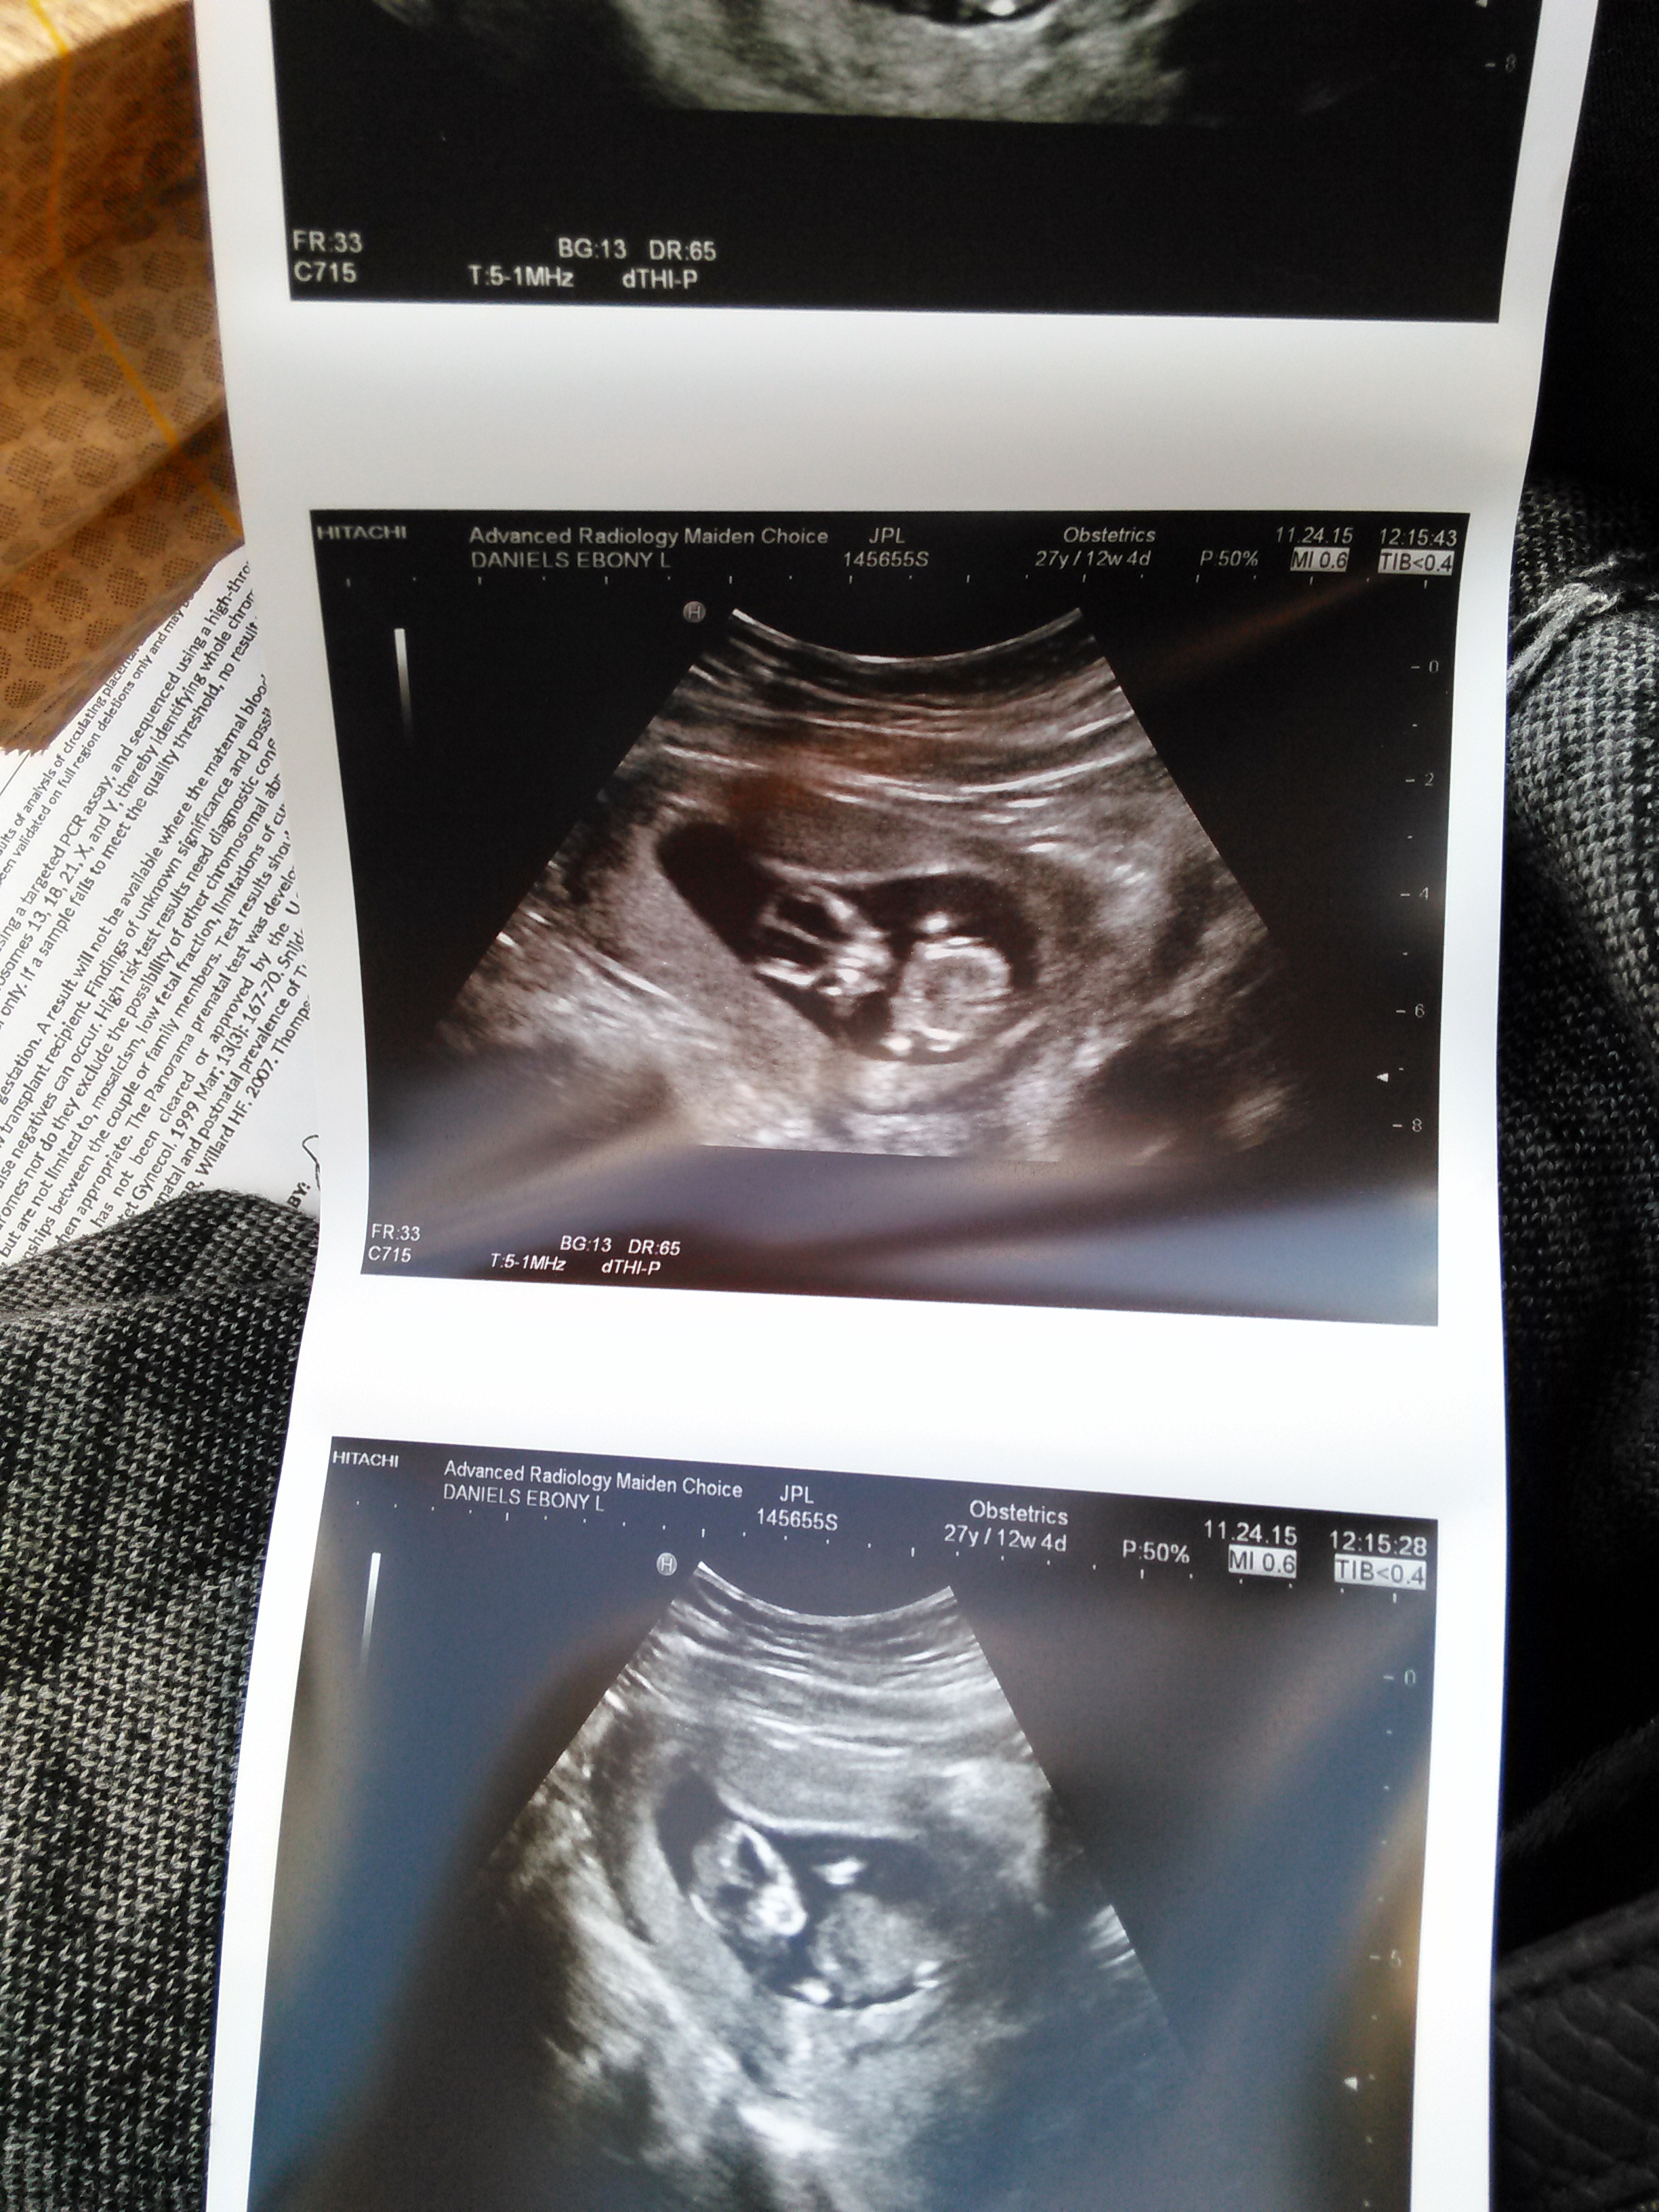

Twins!!!!!! I had two ultrasounds, one week apart.